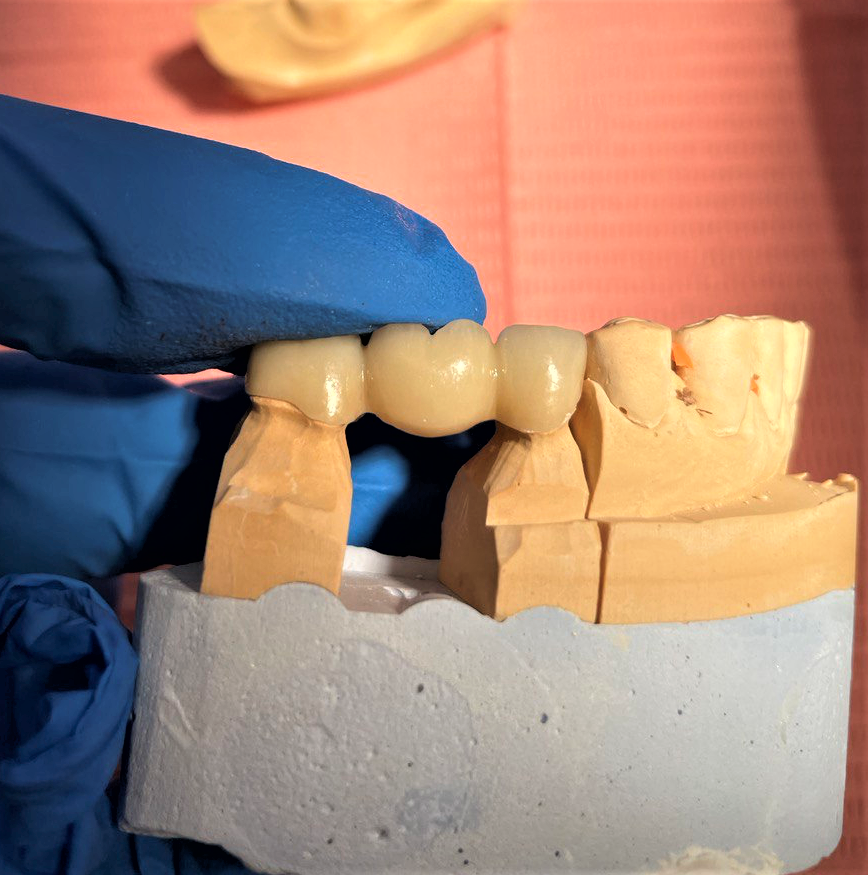

Не можем сдать мост. Вы такое можете представить? Мост из трёх единиц. Два опорных зуба и один промежуточный. Что может быть проще?

Попытка номер 2.

Новое творение гениального мастера.

Ужасно. Стало просто ужасно. Хуже, чем раньше. Курица лапой сослепу ваяла этот шедевр.

Разбор. Ну ведь очень не симпатичная конструкция. Ещё и с косяками.

Все наши замечания пропущены мимо глаз и мимо ушей. Такую работу сдать пациенту - себя не уважать.